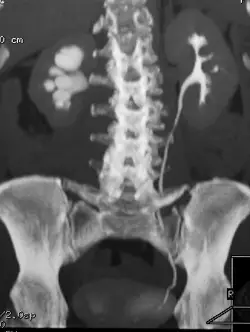

30.顯影電腦斷層檢查如下圖,下列敘述何者最適當?

AA.multiplanr reformat image of coronal nephrogenic phase image

BB.maximal intensity projection of coronal excretory phase image

CC.maximal intensity projection of sagittal nephrogenic phase image

DD.maximal intensity projection of sagittal excretory phase image

- 解剖切面判定 (Anatomical Plane):影像呈現人體的正前方視角,中央為腰椎(lumbar spine),兩側可見雙側腎臟,下方為骨盆腔(pelvis)。此為明顯的「冠狀切面(coronal plane)」,而非從側面觀看的矢狀切面(sagittal plane)。

- 影像重組技術 (Reconstruction Technique):影像中的骨骼結構與充滿顯影劑的泌尿道呈現出極高的亮度(高衰減值, high attenuation),且影像具有一定的厚度感,能夠將原本立體彎曲的整條左側輸尿管完整顯示在同一個平面上。這種視覺效果是「最大強度投影(Maximal Intensity Projection, MIP)」的典型特徵。MIP 會在選定的視角路徑上,將具有最高 CT 值(HU)的體素(voxel)投影出來,因此特別適合用來觀察對比度極高的血管(CTA)或泌尿道(CTU)。

- 顯影時相判定 (Contrast Phase):觀察對比劑(顯影劑)的分佈位置,可以發現高密度的對比劑已經大量充